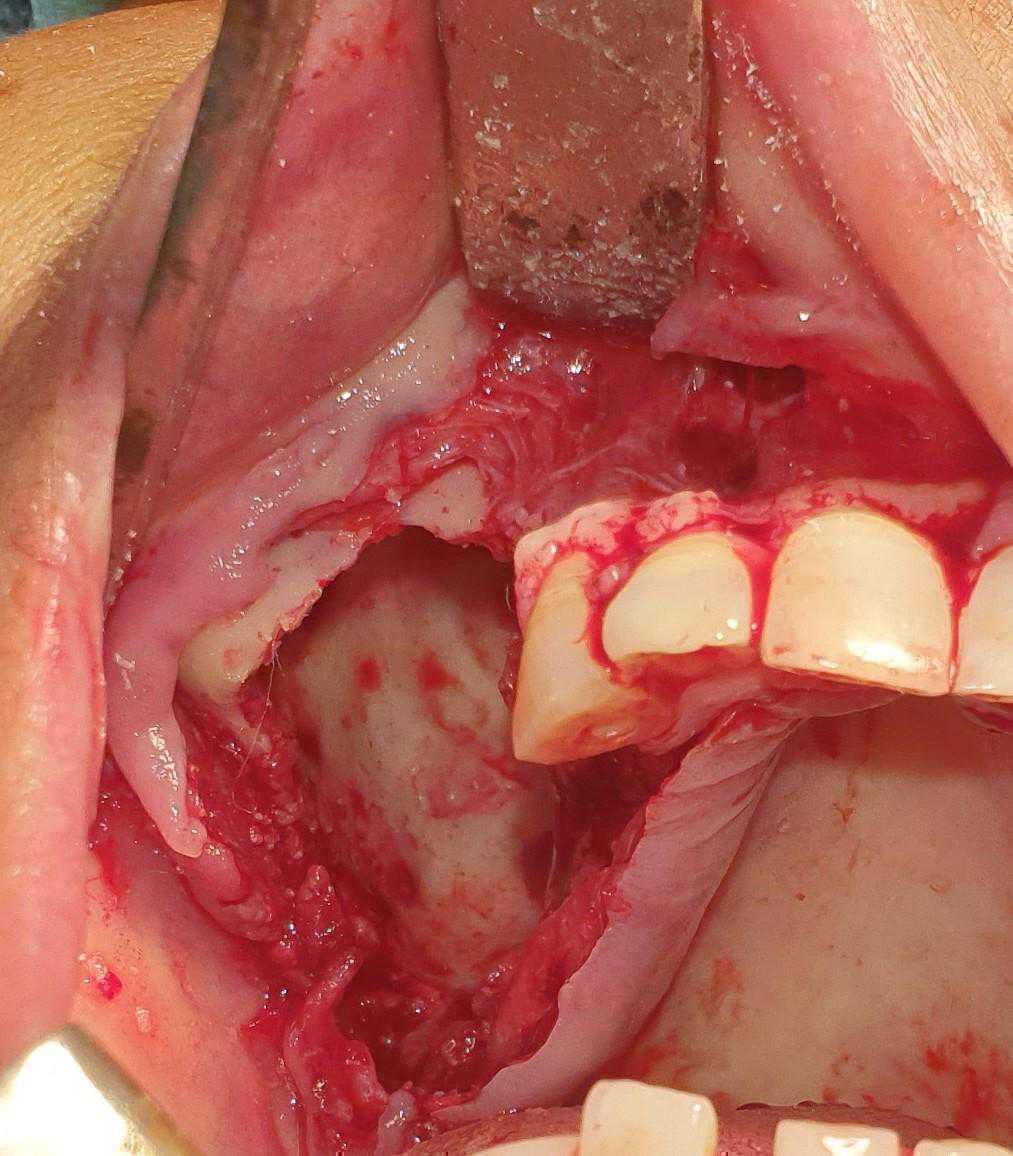

This is a case of Ameloblastic Fibro-Odontoma with a long term follow up.

https://demo.discussdentistry.com/forums/topic/post-mucormycosis-avascular-necrosis-of-maxilla-rehabilitation-with-zygomatic/#post-24499 <![CDATA[Post Mucormycosis Avascular necrosis of maxilla, rehabilitation with Zygomatic]]> https://demo.discussdentistry.com/forums/topic/post-mucormycosis-avascular-necrosis-of-maxilla-rehabilitation-with-zygomatic/#post-24499 Thu, 25 Aug 2022 12:14:40 +0000 Sankalp Mittal

• 20210604_101325 (2)20210604_101317 (2)20210604_103315 (2)20210604_102857 (2)20210604_104202 (2)20210604_104853 (2)20210824_105656 (2)20210824_112353 (2)20210824_114957 (2)20210824_131302 (2)20210826_100648 (2)20210826_100749 (2)20210826_100919 (2)20210914_183943 (2)20211001_17535220211012_18543620211012_192043 (2)20211012_185627 (2)20211012_195430 (3)20211027_193725 (2)20211027_200729 (2)20211027_200919